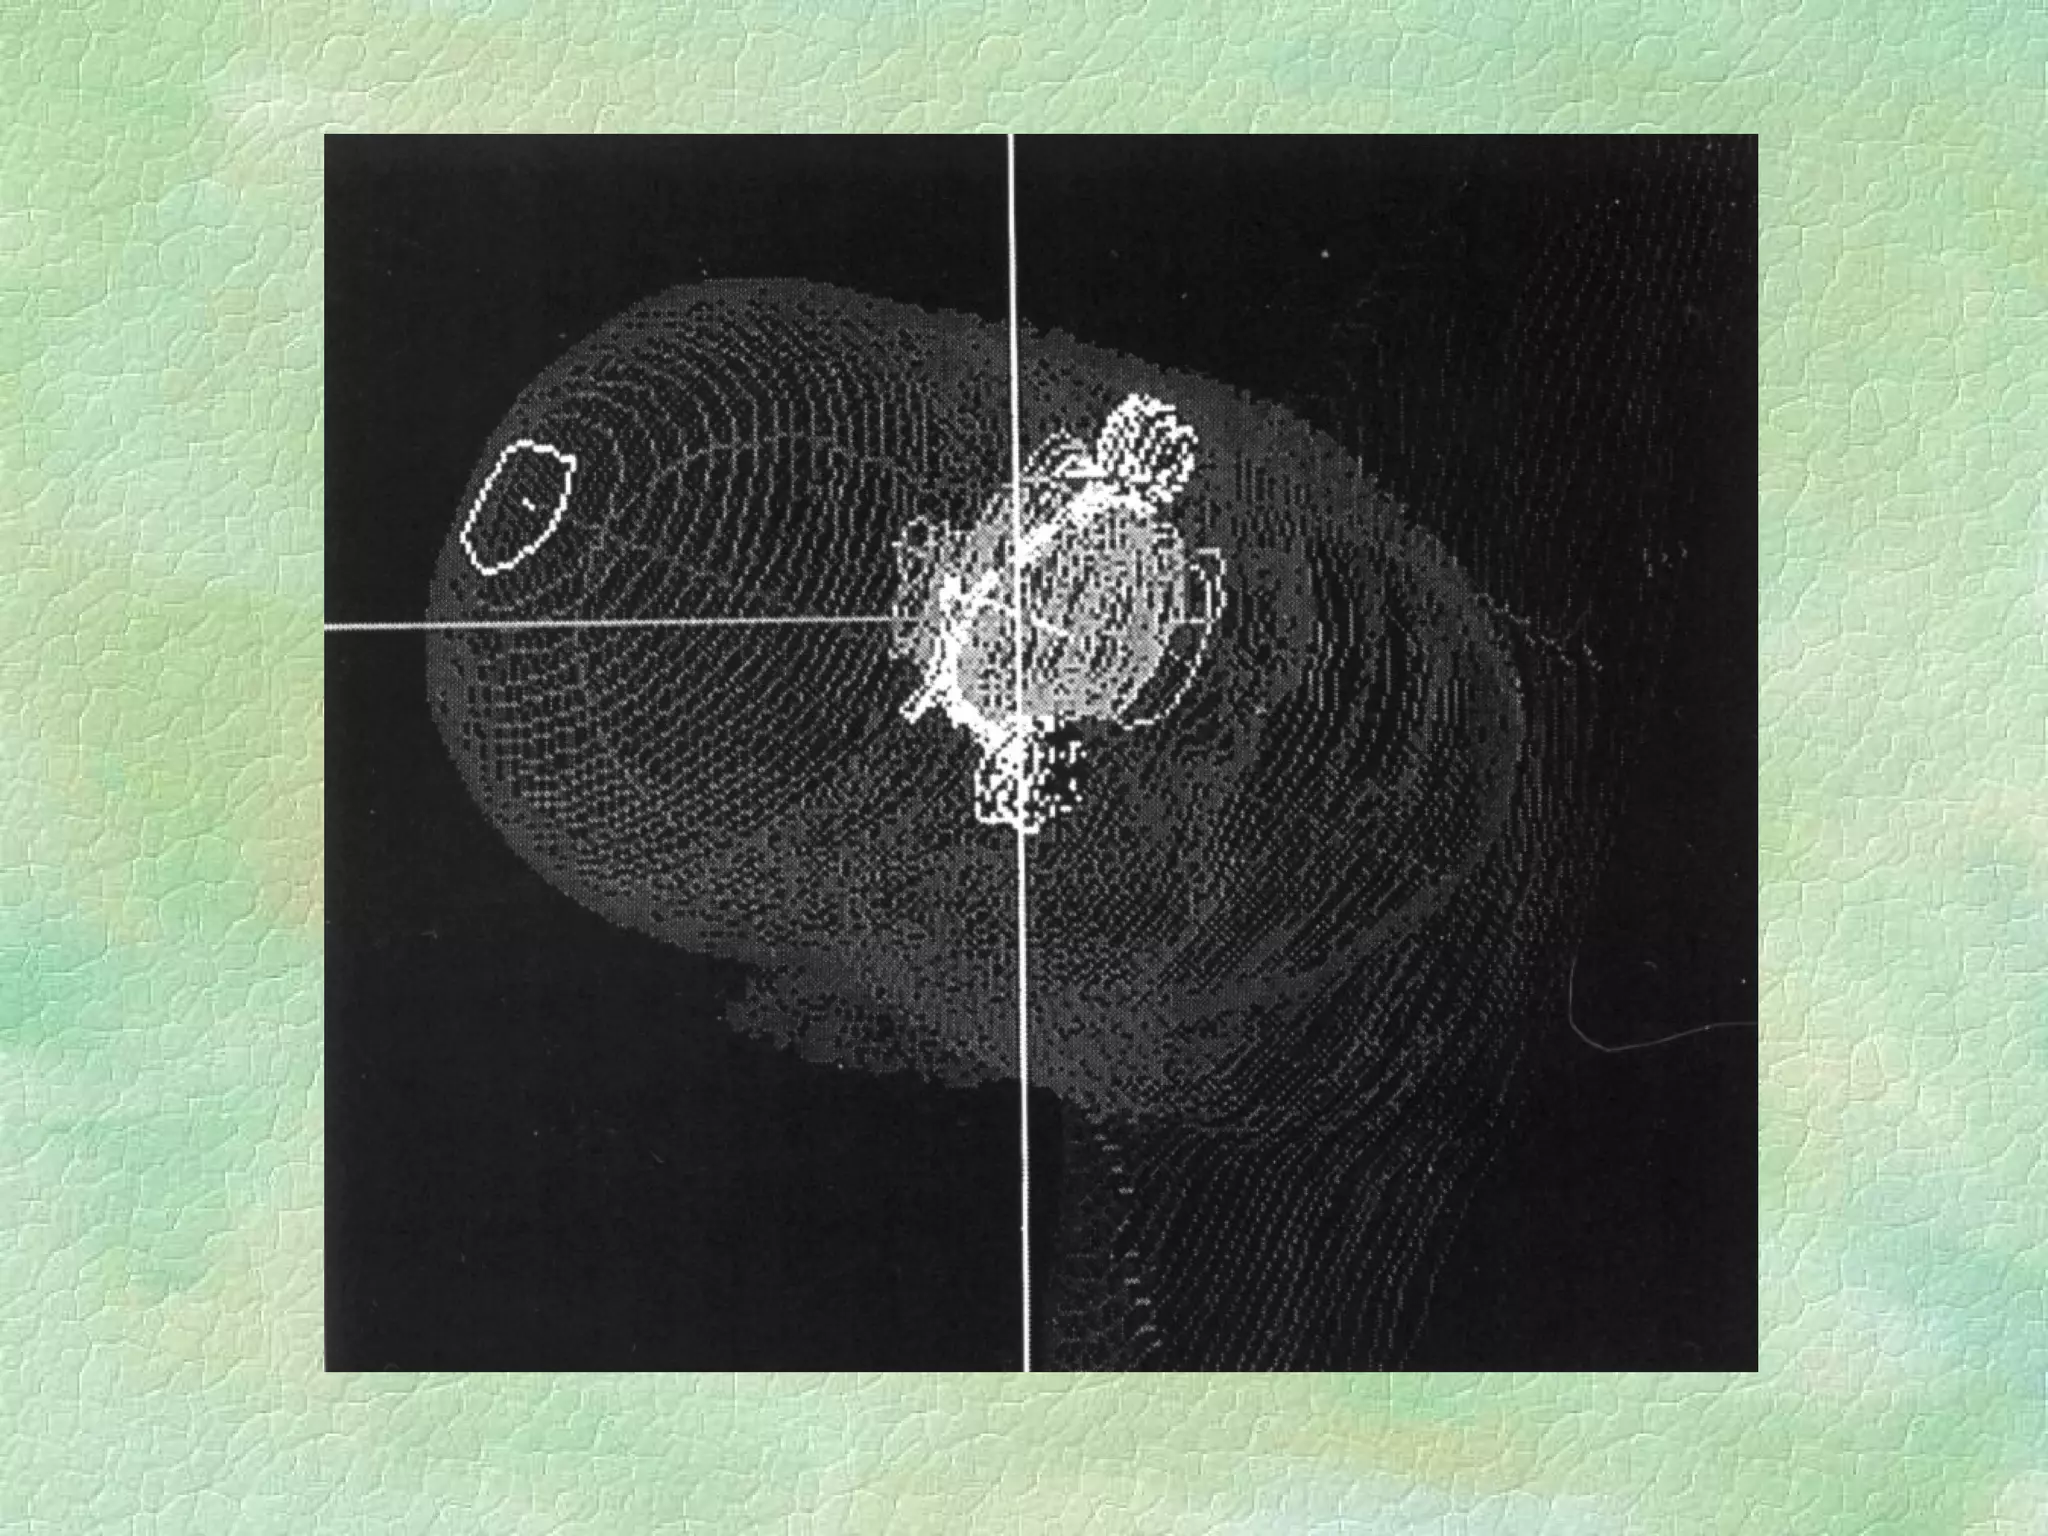

Virtual Simulation: -  Immobilization CT Coordinate system Structure Delineation Isocentre localization Beam placement/definition

Problems: Images are static and organ motion is not evident Correlation of imager/patient/treatment coordinate systems is non-trivial - DRRs Resolution of data set is limited by slice thickness - structure definition/DRR Imaging modality - image fusion